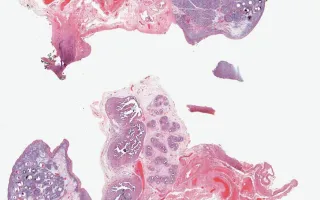

Ovary, Gonadoblastoma, H&E stain

This 6 year old girl was found to have XX/XY mosaicism during a postnatal workup as a follow up to a triple screen which suggested trisomy 18. She had bilateral salpingo-oophorectomy performed as prophylaxis for a potential malignancy.

Gonadoblastoma is a tumour of immature gonadal sex cord and germ cells, which is considered a precursor lesion of malignant germ cell neoplasia. It is almost always associated with intersex-associated gonadal abnormalities, for example when Y chromosome material is present within an ovary. Approximately 80% of patients are phenotypically female (45X/46XY, 46XX/46XY). It is typically bilateral in the setting of dysgenetic gonads. Gonadectomy is the treatment of choice with excellent prognosis.

The sections demonstrate a mix of male and female gonadal structures (seminiferous tubule formation, epididymis and fallopian tube). There is ovarian cortex-type stroma and a few scattered gland-like structures. No primordial or primary follicles are present. The seminiferous tubule-like structures contain a small amount of Leydig cells and are lined by Sertoli cells (inhibin positive) with some immature germ cells (Oct3/4 positive). There are some well-defined, basement-membrane lined, round nests of large, pale seminoma-like cells admixed with small dark, angular, sex cord cells. Oct3/4 stains most of the germ cells.

This slide shows H&E stain. See Related Content for inhibin and Oct3/4 stains.